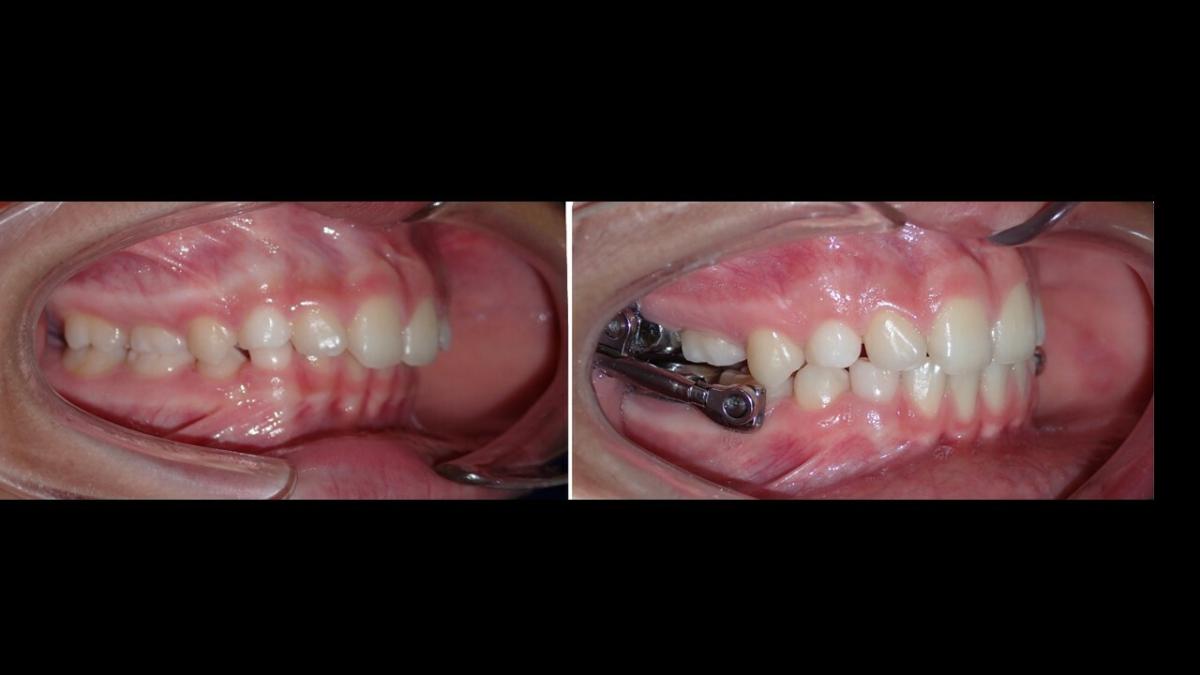

Galería de Sonrisas

large-Resultado de avance de la mandibula